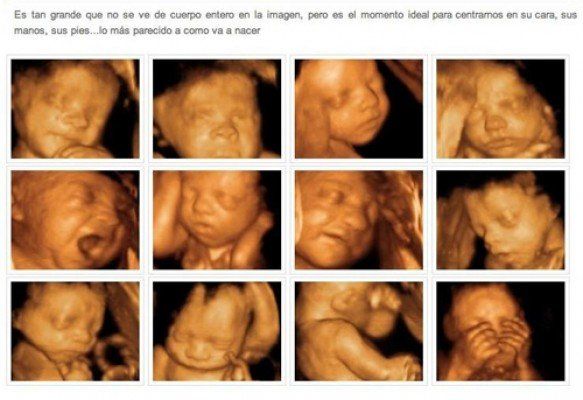

Conozca el excelente trabajo que desarrollamos en relación a la medicina fetal. Realizamos ecografía temprana del embarazo, crecimiento del embrión, entre otros servicios.